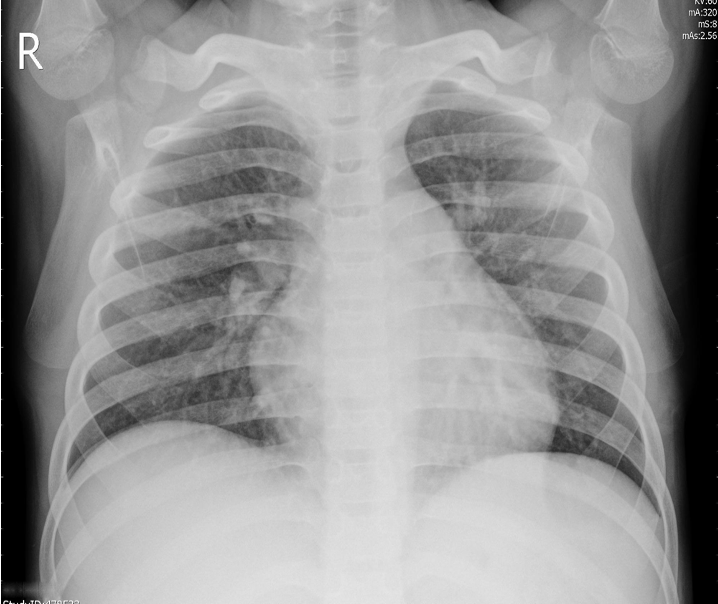

Figure 2 exemplifies two healthy lungs (upper two) and two lungs suffering from pneumonia (lower two). All images of the data set are recorded with different resolutions. Therefore, we convert the images to greyscale and compress them to 128128 pixels. We allocate 1,500 images to the training set, 200 to the validation set, and 1,400 to the test set.